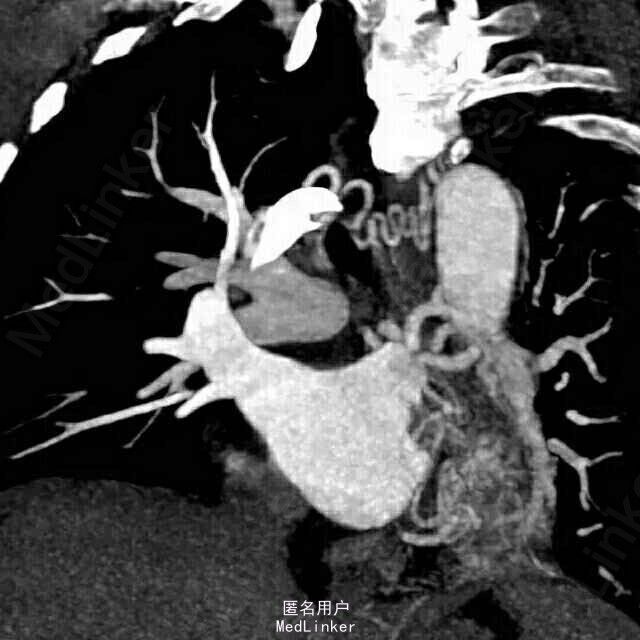

女,50岁。 间断咯血25年余,加重1月,行肺部增强CT。

患者胸部增强CT及血鬼重建影像学表现包括:边界清晰、病变有主动脉分支供血、病变静脉引流入肺静脉。

考虑影像学诊断为:肺隔离症

左肺下叶内前基底段脊柱旁可见斑片影,边界清晰,其内可见支气管气相,平扫密度尚均匀,增强后病变内强化不均匀,可见多发血管影,血管重建示病变由主动脉弓及降主动脉迂曲增粗的小分支供血,可见一直粗大静脉引流入左肺静脉。根据病变部位,供血动脉来源于体循环,静脉引流入肺静脉,此例为典型肺隔离症,已被术后病理所证实。 肺隔离症是一种先天性肺发育畸形,主要特征是部分胚胎肺组织与正常肺组织隔离,病变肺组织的动脉供应由体循环直接分出的动脉分支供应,静脉回流至肺静脉或体循环。尽管其表现多种多样,体动脉向肺组织供血为其最特征表现。常分为叶内型及叶外型2种,最常见为叶内型,多为体动脉单支血管供血,无单独胸膜包裹。叶外型有单独胸膜包裹,多位于膈肌下,由肺或体血管供血,血管较小,多伴有其他先天畸形。本例为叶内型,隔离的肺组织易反复发生感染,出现相关临床表现。 肺炎主要表现为肺实变或不张,常伴有病变周围斑片或淡片影,边界可不清晰,临床症状有助于诊断。 肺癌侵犯病变内及周围血管、支气管,造成支气管闭塞伴远端阻塞性炎症,肺门及纵隔常见肿大淋巴结。 支气管扩张伴感染时可见扩张的支气管,可为管状、串珠样或囊泡状,病变周围感染呈斑片影,边界欠清晰。